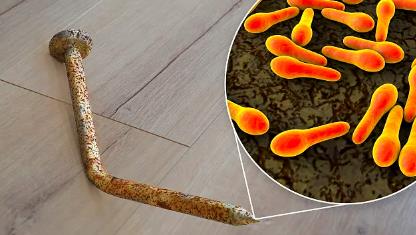

易拉罐对嘴喝感染鼠尿病:从发病到去世仅4天